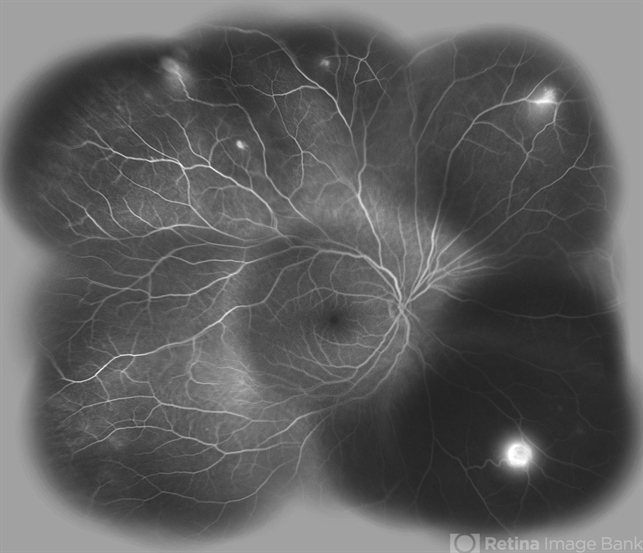

- Von Hippel-Lindau, exudative retinal detachment, retinal angiomatous proliferation (RAP)

- Soodabeh Fooladin, Negah Eye Center, Tehran

- Imaging device

- Heidelberg Spectralis

- Wide field FA image of the right eye of a 25-year-old woman with retinal angiomatosis (Von Hippel-Lindau). Fundus of the right eye seemed to be normal in ophthalmoscopy.